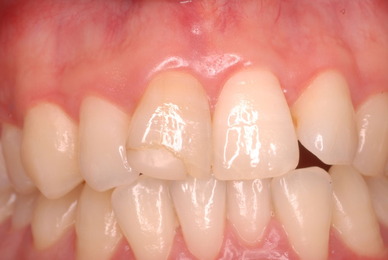

歯周病の疑いで東京のかなり遠方の方が来院されました。

驚くべきことですが、定期検診は受けていたそうです。しかしながら歯周病の指摘は受けたことがないそうです。

何故か?定期検診が虫歯のチェックのみになり、又肝心の歯周病の検査や歯周病の部分の予防や治療のためのブラシの使い方などを学んだ事がないのです。